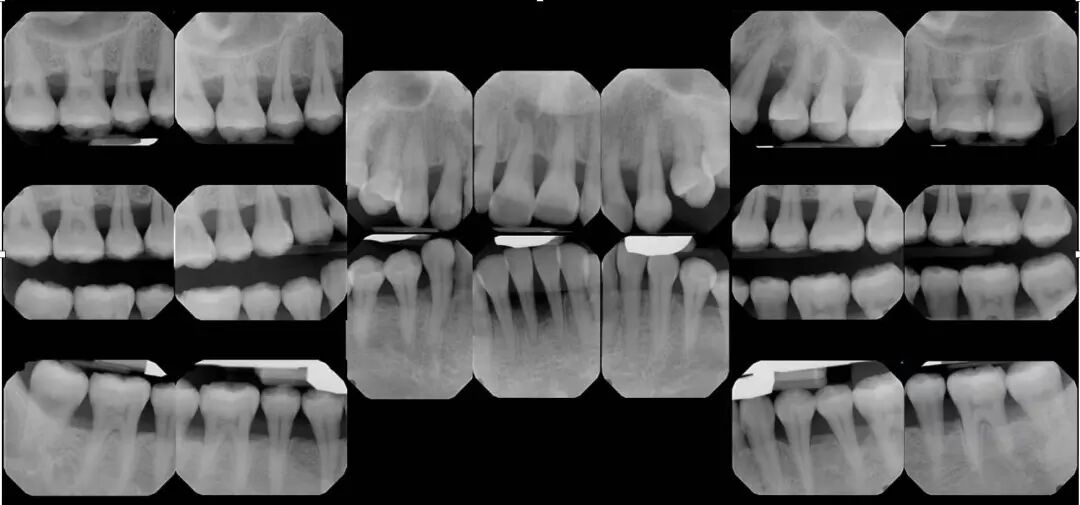

五. 诊断牙周炎需要做哪些检查?